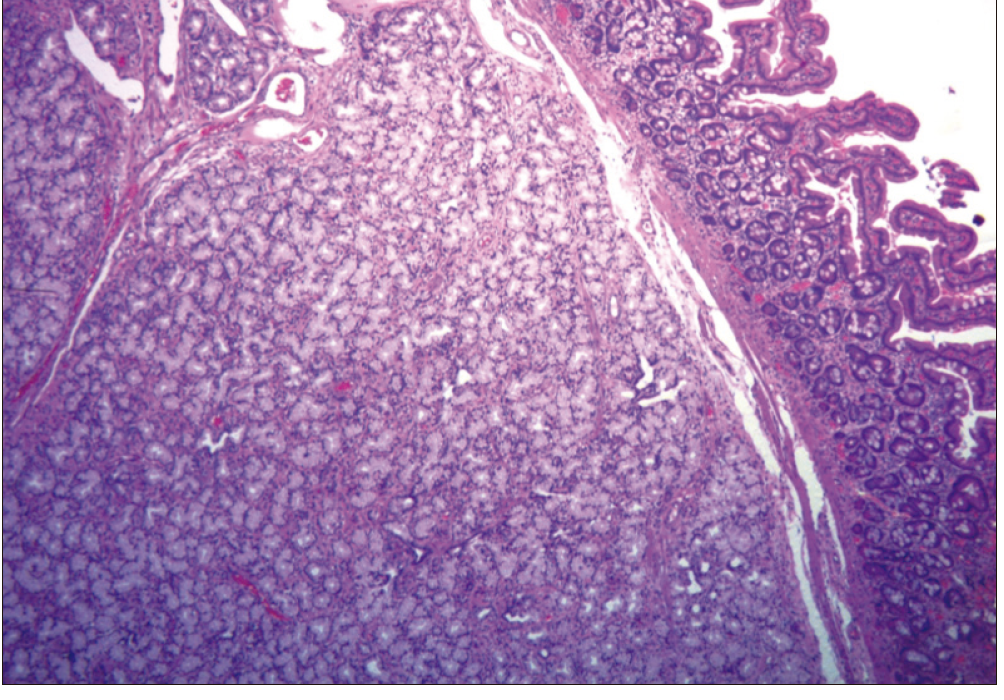

En diferido se realizó la resección endoscópica del pólipo a través de una enteroscopia por empuje (push), mediante la utilización de un asa caliente previa inyección del pedículo con adrenalina 1:20000. El informe de la anatomía patológica evidenció una proliferación de glándulas mucosas tapizadas por células columnares con disposición nodular y patrón de crecimiento expansivo a nivel de la mucosa y la submucosa, compatible con un adenoma de las glándulas de Brunner sin displasia histológica evidente (Figura 4).

Figura 4. HyE 40 X. A nivel de mucosa y submucosa se observa una proliferación de glándulas

mucosas tapizadas por células columnares con núcleos monomorfos, de disposición nodular y crecimiento

expansivo, compatible con Adenoma de las glándulas de Brunner